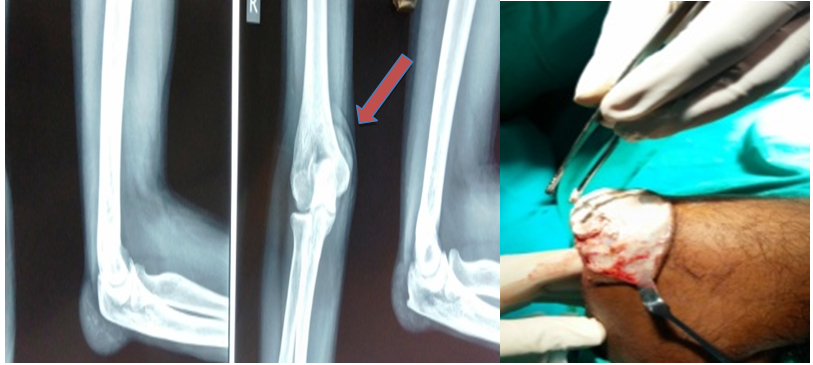

Clinical examination plays key role in streamlining and narrowing the differential diagnosis after the clinical history. Although there was a clear history of ignored gout treatment at patient’s end, we could still not rule out the possibility of multiple soft tissue swellings around the elbow due to other differential diagnosis in mind as a systematic approach. Bilateral elbow radiographs were done as routine and a postero-medially extending shadow may be seen in the anteroposterior radiograph of right elbow (Figure 2). Fine needle aspiration cytology revealed chalky material- crystal deposits, surrounded by lymphocytes, giant cells and occasional red cells. Radiographs did not show any intra-articular involvement. Bilateral elbow joint aspirate revealed gouty crystals (monosodium urate, MSU) that is a pathognomonic feature. C- reactive protein was raised (80) and ESR (erythrocyte sedimentation rate) was 18. The CRP levels gradually decline over 3 weeks to <5. There other significant finding in the full blood count.

Figure 2 The arrow shows the mass extending postero-medially and compressing on the ulnar nerve causing patients paraesthesia symptoms. Posterior approach to dissect and expose the whole mass.

Treatment

Both pharmacological and surgical interventions are important in this case scenario. Under appropriate anti-uricaemia medication (Allopurinol 300mg daily was given for advanced hyperuricaemia with uncontrolled tophaceous growth, till the symptoms subsided and then maintenance dose of 100mg daily along with a regular scheduled Rheumatology follow up advised), a meticulous surgical excision was performed for bilateral elbow swellings by standard posterior approach (Figure 2). Careful dissection and meticulous separation of tophi from the underlying soft tissue external to the cubital tunnels. The tophi were external to the cubital tunnel but found compressing the nerve underneath and indirectly causing cubital tunnel compression neuropathy due to mass effect. Hence both the cubital tunnels were also decompressed to release the pressure off the compressed nerve. The nerves were not transposed and left in the anatomical location. The surgery was performed on bilateral elbows in the same sitting by two Orthopaedic surgeons and assistants. Histopathological examination was done, and diagnosed to be tophaceous gout. The tophi are displayed in Figure 3 below. Post-operatively patient had immediate reduction in symptoms and normal distal neurovascular status.